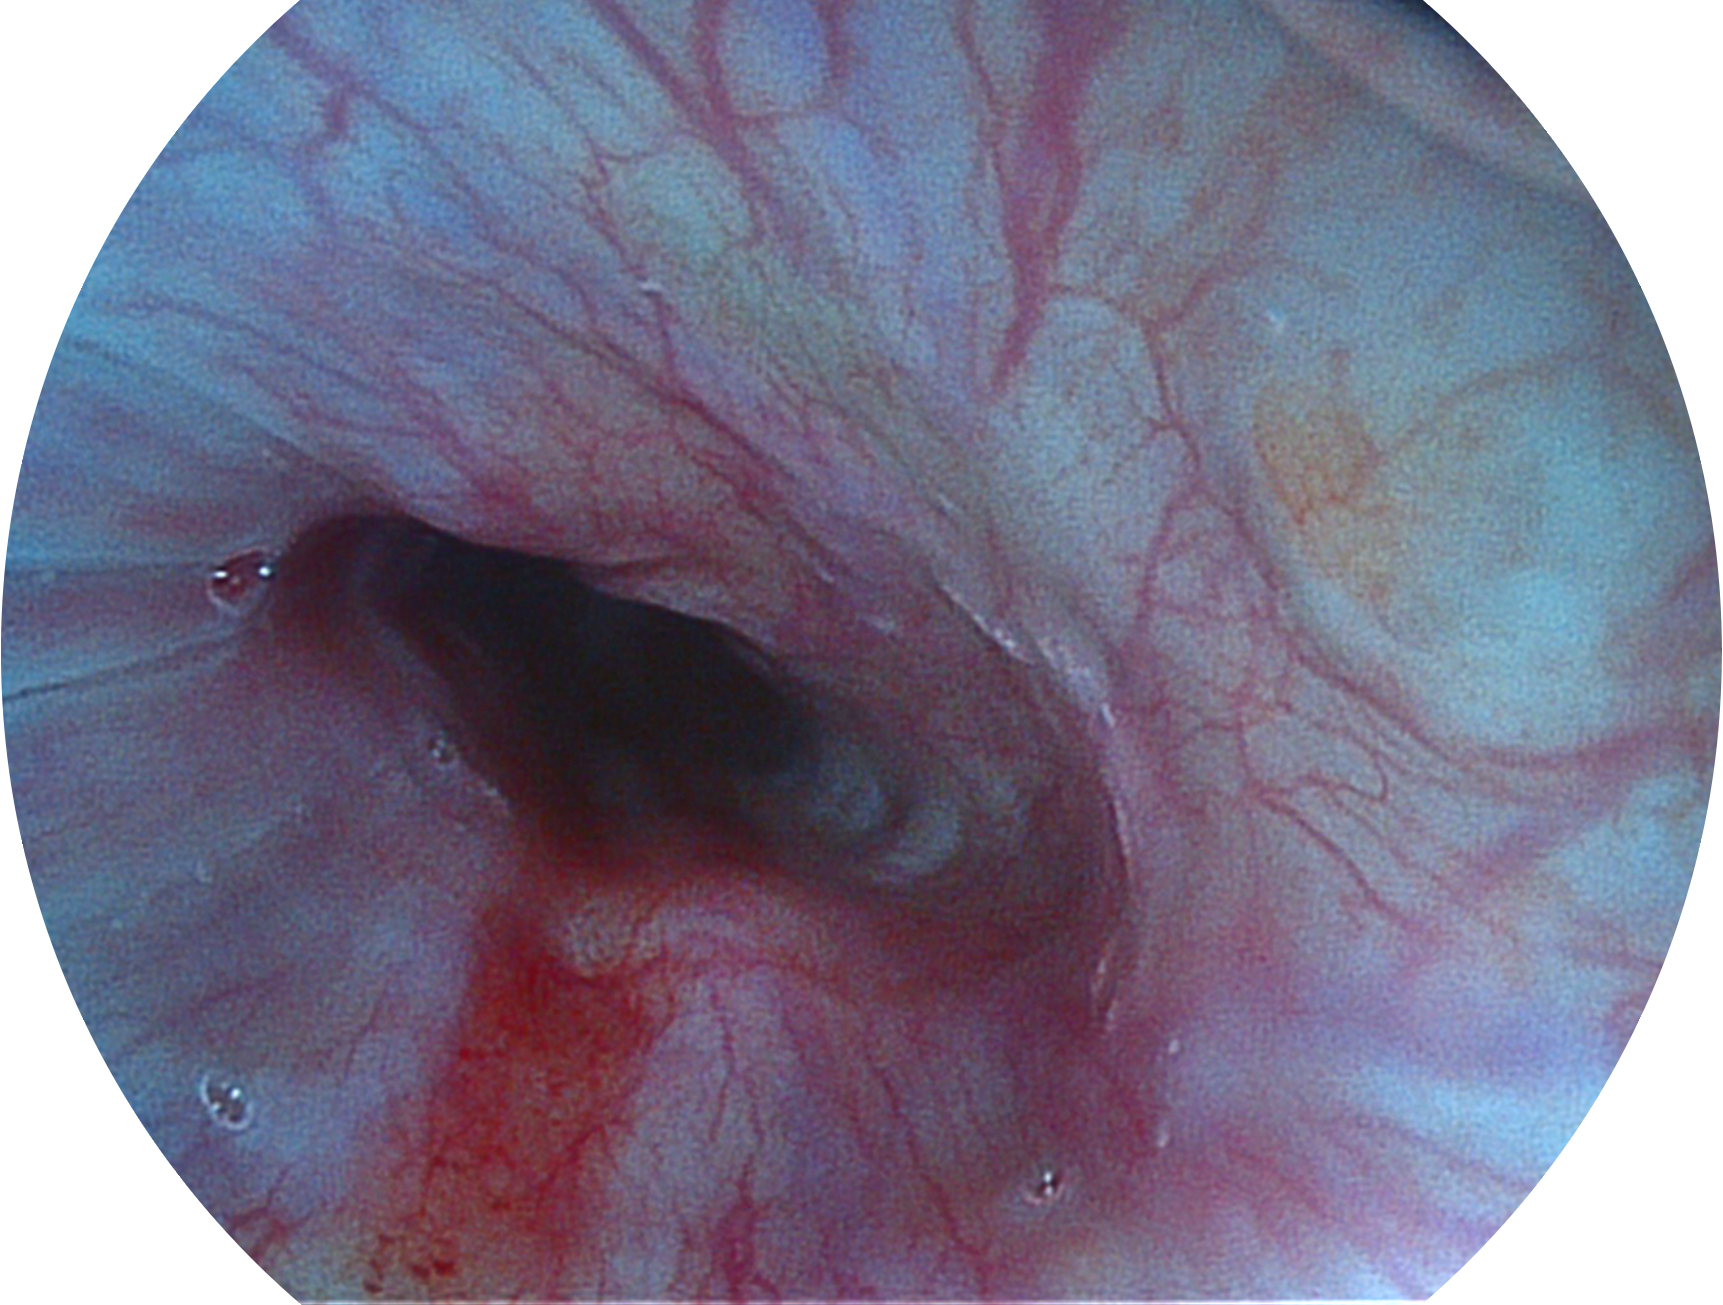

亚星官网新开发的内镜染色技术,主要是基于多波长LED 光源的开发,VLS-55Q 四波长LED 光源是由四个不同颜色的LED光按照相应照明模式所规定的特定发光比例进行合束后形成,合束后形成的照明光的光谱由红光、绿光、蓝光及蓝紫光这四个不同的波段范围构成。具有更高光谱自由度,通过光谱比例的控制,实现了聚谱成像技术,英文全称为“Spectral Focused Imaging, SFI”,缩写为“SFI”和光电复合染色成像技术,英文全称为“Versatile Intelligent Staining Technology, VIST”,缩写为“VIST”。